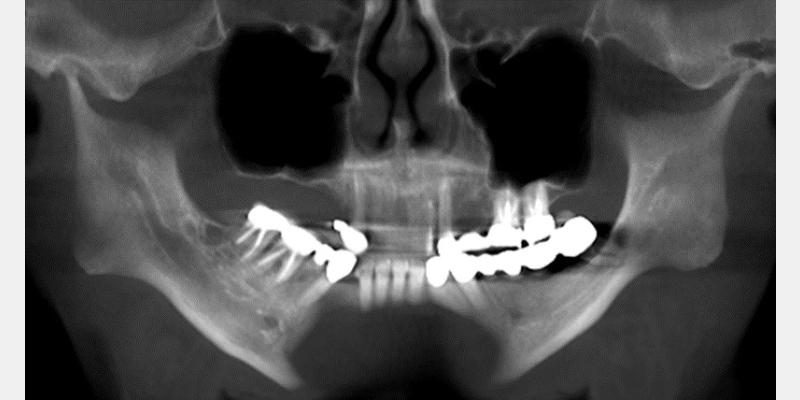

George, a 57-year-old male (Fig. 1), has small condyles, which usually correlate to an injury to the TMJ occurring before growth is complete. In a 2006 journal article, Carlos Flores-Mir and Brian Nebbe1 discuss an atypical TMJ disc abnormality associated with reduced forward growth of the maxillary and mandibular bodies.

In many cases, they studied, reduced maxillary and mandibular growth resulted in a compromised oropharyngeal airway space. (Fig. 2)